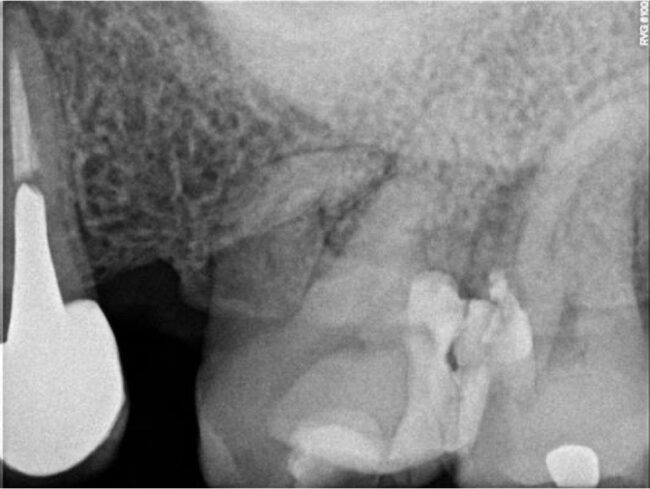

Organizado por O2O Endo Academy, los doctores Francisco de la Torre y Rafael Cisneros han sido los encargados de impartir este curso teórico-práctico en el que se han dado todas las claves para una endodoncia paso a paso.